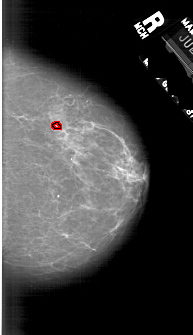

A_1740_1.LEFT_CC

FILE: A_1740_1.LEFT_CC.OVERLAY

TOTAL_ABNORMALITIES 1

ABNORMALITY 1

LESION_TYPE CALCIFICATION TYPE PLEOMORPHIC DISTRIBUTION CLUSTERED

ASSESSMENT 4

SUBTLETY 5

PATHOLOGY BENIGN_WITHOUT_CALLBACK

TOTAL_OUTLINES 1

BOUNDARY